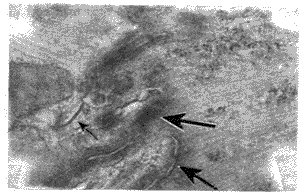

图5为AC组肥大心肌细胞间ID和GJ,与对照组相比,PF面颗粒直径无明显改变,但排列紊乱,数量减少,颗粒中心与中心距离变大,未见有弥散的小的缝隙连接分布。

图5 AC组肥大心肌细胞的ID,箭头所示为GJ、PF面颗粒排列紊乱,尤其是边缘部位颗粒数量减少 ×60000